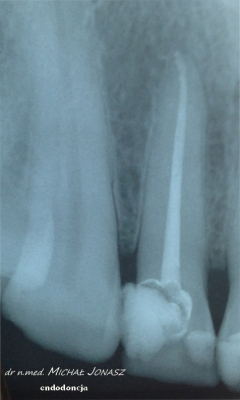

Zmiany okołowierzchołkowe to ogniska zniszczenia kości wokół wierzchołków korzeni zębów. Przewlekłe, nieleczone zmiany zapalne w obrębie korzeni zęba mogą powodować duże uszkodzenia kości i skutkować utratą zębów. Reendo polega na usunięciu materiału, którym wypełnione są kanały i zlokalizowaniu nieprawidłowości, czyli niedostatecznie oczyszczonego lub wypełnionego kanału albo pozostawionego, złamanego narzędzia w jego świetle. Dzięki mikroskopowi problemy anatomiczne, takie jak wąskie, zarośnięte kanały, zakrzywione korzenie, boczne, nietypowe odnogi są możliwe do wyeliminowania.

Diagnostyka obrazowa i wprawne oko Stomatologa są podstawą do podjęcia powtórnego leczenia kanałowego. Wychwycenie zmian patologicznych kierujących na powtórne leczenie kanałowe często jest efektem wnikliwej analizy zdjęć RTG. Powtórnego leczenia kanałowego wymagają zęby, których kanały korzeniowe nie zostały prawidłowo wypełnione. Im dłuższy czas upływa od zakończenia pierwotnego leczenia kanałowego, tym mniejsza szansa, że ząb da o sobie ponownie znać. Nieprawidłowo przeleczony kanałowo ząb, to potencjalnie ogromne ryzyko dla pacjenta. Ząb źle leczony kanałowo przypomina o sobie po wielu latach, bądź w postaci dolegliwości bólowych, bądź przez wolno, bezobjawowo rozwijającą się torbiel. Wytworzenie się torbieli wymaga już interwencji z zakresu chirurgii stomatologicznej. W takiej sytuacji po leczeniu powtórnym pacjent jest kierowany do chirurga na zabieg wyłuszczenia torbieli.

Na zdjęciu RTG efekt leczenia endodontycznego można ocenić po 3 – 6 miesiącach. Każde kanałowe leczenie należy systematycznie kontrolować poprzez wykonywanie rutynowych zdjęć radiologicznych, tak by zawczasu uniknąć nieprzyjemnych problemów.